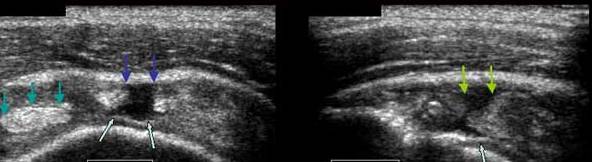

ENTORSA ACROMIOCLAVICULARA

Epansament hipoecogen in sistemul capsulo-ligamentar→

Cu discreta hiperemie la Doppler

Comparatie cu aspectul normal al articulatiei→

Radiografic- aspect normal →